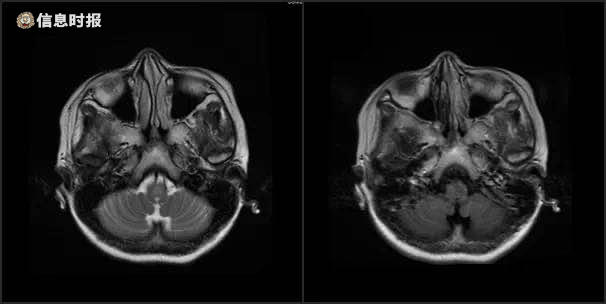

该院接诊的神经内一科主任王展航考虑患者有明显消化道症状,且影像检查资料提示有延髓及颈髓病变,认为是中枢神经系统脱髓鞘脑病的可能性较大。随后,其脱髓鞘相关抗体检查提示为阳性,进一步证实了王展航的判断。“最终明确诊断为视神经脊髓炎。”王展航说。

影像检查资料提示有延髓及颈髓病变